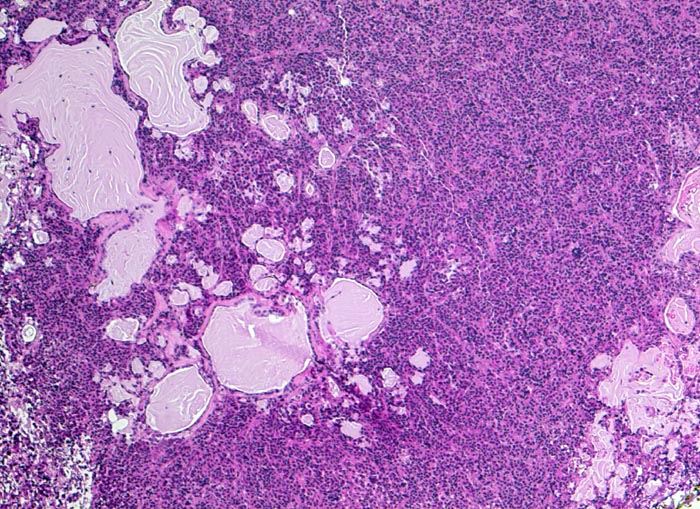

diffus wachsendes chromophobes Hypophysenadenom

benigner Tumor

Hypophyse, Vorderlappen

Vereinzelte epithelialisierte Zysten, sehr wahrscheinlich der Pars intermedia entsprechend. Daneben ein diffuses Tumorinfiltrat aus kleinen zytoplasmareichen Zellen.

Expression von Prolactin in 100% der Tumorzellen (Prolactinom), herdförmiger Expression von ACTH in isolierten Zellen und in vereinzelten Tumorzellverbänden. Expression von Beta-TSH in isolierten Tumorzellen. MIB-1-Index weit unter 1%.

Hypophysenmakroadenom mit erhöhtem Prolaktinspiegel